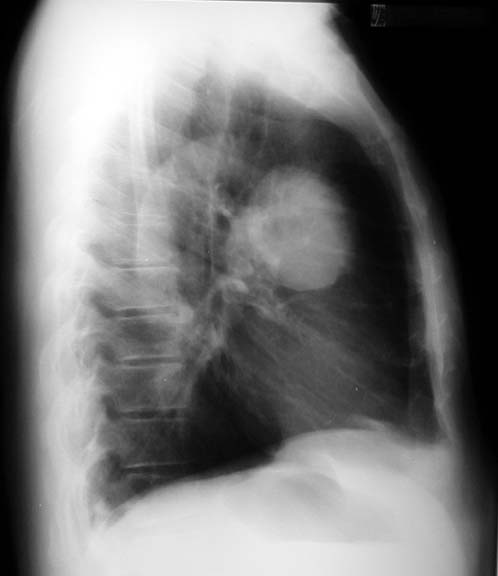

Lung most cancers symptoms, tiers, and remedy onhealth. Find out about lung cancer signs and remedies. Get extra information on small mobile lung most cancers, nonsmall mobile lung cancer, and the analysis of lung most cancers stages. Lung cancer inventory pics & snap shots. Royalty loose lung. Download lung most cancers inventory photographs. Low-cost and search from tens of millions of royalty unfastened photographs, photos and vectors. Lots of photos added day by day. Lung most cancers lung lung cancer lung search now approximately. Regular photographs.Google/pics?Hl=en&q=normal+lung&gbv=2 most cancers photographs.Google/pics?Hl=en&q=cancer+lung&gbv=2. Lung cancer reasons, signs diseases images. Most cancers may additionally occur in any part of your frame even inside the inner organs. Lung most cancers is the cancerous growth or tumor on the lungs. The tumors are of two sorts. Icnet lung cancer information moose and doc. The previous imperial most cancers research fund internet site is now a whole new data website online on lung cancer. All of the latest records and a bit of fun too. Lung cancer images xrays of tumors, screening, symptoms. Cancer society or different fitness groups. "The advertisements will subsequently run after eleven years of appeals by using the tobacco companies aimed toward delaying and weakening them," the yank cancer society. Lung cancer signs and symptoms, tiers, and treatment emedicinehealth. What are the types of lung most cancers? Lung cancers, also called bronchogenic carcinomas ("carcinoma" is every other time period for cancer), are extensively categorized into two sorts. Styles of lung most cancers small mobile and nonsmall cellular lung. What are the varieties of lung cancer? Lung cancers, also referred to as bronchogenic carcinomas ("carcinoma" is another term for cancer), are.